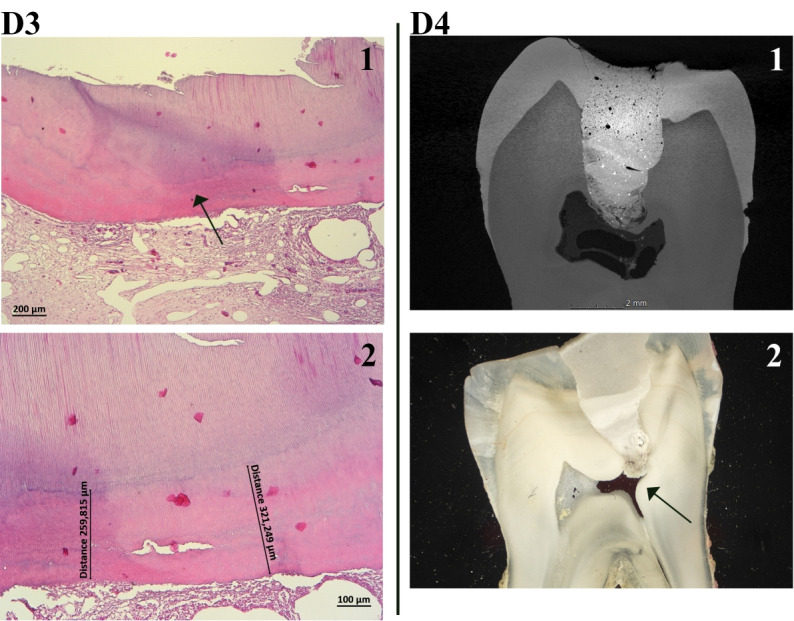

Pulp capping is a vital pulp therapy that aims to prolong the life of a tooth by protecting it after pulp exposure occurred. Pulp capping biomaterials are intended to induce odontoblasts to deposit a natural tertiary dentin barrier to protect the pulp-dentin complex. Two pulp capping agents with calcium silicates in their composition, but with different mechanisms of the setting reaction were tested in vivo with the main objective of comparing their effect on the pulp-dentin complex. The specific aim was to evaluate the preservation of pulp vitality following in vivo direct and indirect pulp capping on eight human third molars. TheraCal LC, a light-cured calcium silicate-based material, was tested both by direct and indirect pulp capping, while the mineral trioxide aggregate (MTA) cement was tested by direct pulp capping. The molars were assessed by micro-computed tomography (micro-CT) and by light microscopy and stereo-microscopy following histological processing of the teeth. Dental pulp vitality testing was performed before tooth extraction. Inflammatory pulp status was performed on light microscopy images and it was investigated the presence of inflammatory infiltrate, edema, vascular congestion and pulp necrosis. Following pulp capping, the MTA cement showed more favorable results, generating the formation of complete or incomplete dentin bridges in all treated teeth, while TheraCal LC induced the formation of dentin bridges in only two teeth. Tooth vitality was preserved in all tested teeth. In conclusion, both materials stimulated neodentinogenesis, with the MTA cement being more effective and presenting a much more favorable biological pulpal response.